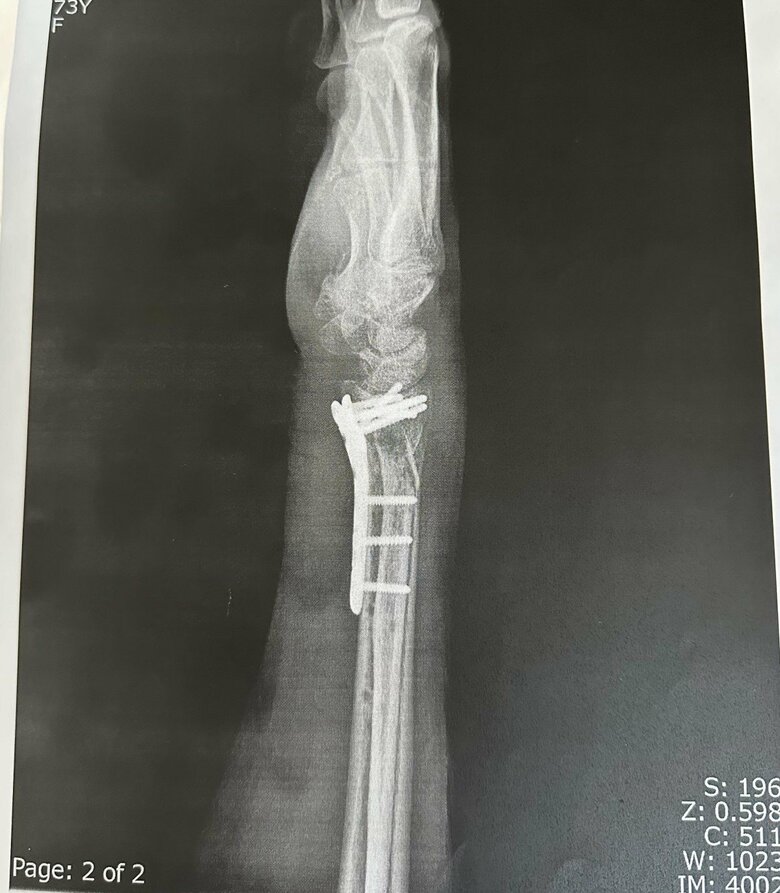

ケガした腕を横から見た図。プレートで腕を固定した

20/22